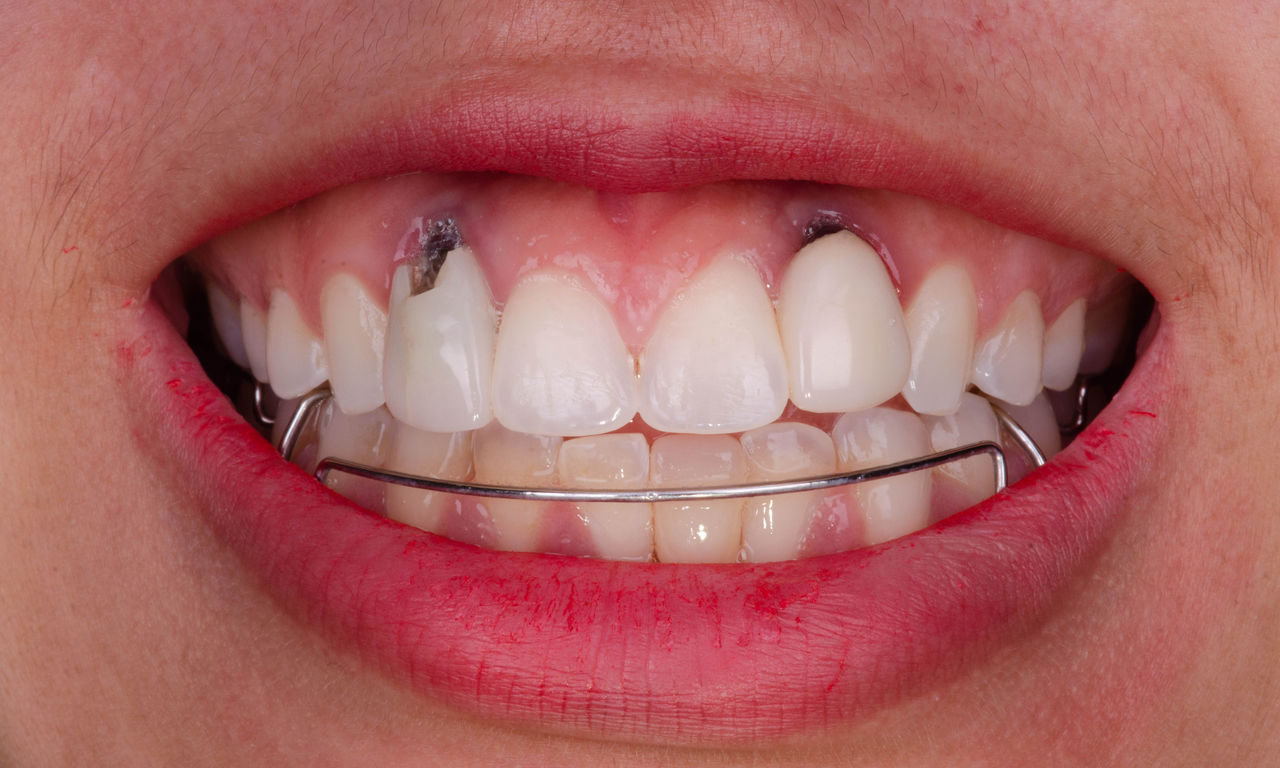

Upper central incisors, in 4 hours

Four IPS e.max CAD single crowns

The restoration with all-ceramic crowns did not require subgingival preparation to cover the margin and no dark metal shadows disturbed the esthetics. With CEREC Primescan and CEREC Primemill patients receive a high-quality all-ceramic restoration faster than ever before.

Before: Inadequate fillings on teeth 12-22, an uneven gingival line on 12 and 11 and incisal edges severely eroded.

After: Four highly esthetic and individualized lithium disilicate ceramic crowns.